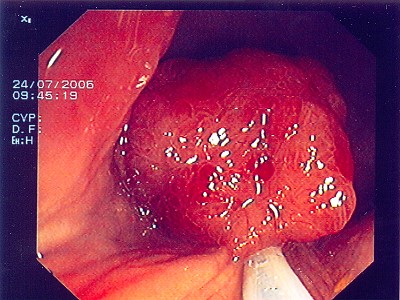

Großer Polyp des Dickdarmes